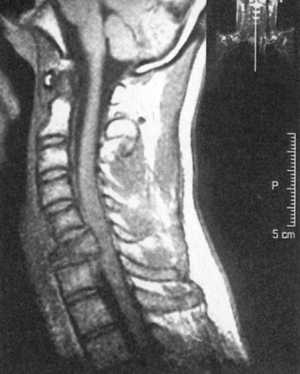

Ценную информацию о состоянии вывихнутых позвонков и спинного мозга дает

МРТ (рис. 2.6, 2.7). МРТ позволяет определить наличие зон ишемии в спинном

мозге (рис. 2.8, 2.9), состояние ликвородинамики (рис. 2.10).

Рис. 2.6. Переломо-вывих скользящий

C5-C6, позвонков со смещением тела С5 кзади с грубой компрессией спинного

мозга на данном уровне |